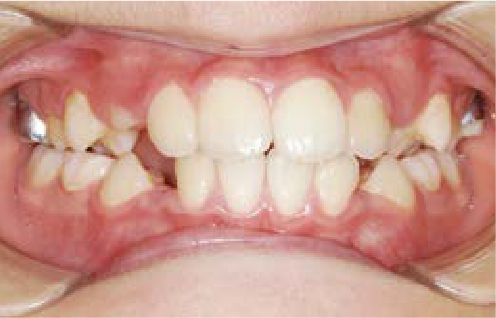

鼻がつまりやすく、口呼吸をしているために上あごが狭い状態でした。また上の前歯がかなり前へ傾いているため、お口をきちんと閉じていることができません。さらに、下の前歯もでこぼこしていました。

治療を終えて

装置によって上あごを拡大し、下あごを少し前へ成長させたことで、永久歯がきれいに並ぶスペースを確保しました。また、お口の機能が向上したことから鼻がよく通るようになり、口呼吸も改善され口も閉じやすくなったので顔の表情もよくなりました。

主訴・治療内容 下あごが後ろに下がり、出っ歯のようになっていることを心配して、無料相談に来院されました。